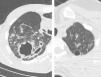

Thick wall cavities were significantly more common in the MDR group, whereas thin wall cavities slightly more common in the NTM group (Fig. 2). From another point of view, cavities of the MDR group mostly appear as cavitary consolidation while in the NTM group as cavities with satellite nodules, with significant difference between these two groups (Fig. 3). Multiple cavities in the NTM group have more homogenous lobar distribution whereas in the MDR group cavities were significantly more common in the right upper lobe (RUL) than in the middle and inferior lobes. Also multiple cavities in RUL were notably more frequent in MDR group than NTM group.

It is told that multiple cavities are even more common in MDR-TB than in drug-sensitive TB: 40% in MDR-TB versus 11% in drug-sensitive TB according to a study.13 In this study multiple cavities were more common in MDR-TB, but neither statistically significant nor differentiating. This different result is probably caused by long delay of NTM species diagnosis and can manifest that multiple cavities can also be produced by NTM in case of chronic illness without any appropriate treatment. Anyway, it seems that shape and distribution of cavities are more differentiating and reliable factor because NTM causes thin wall cavities mostly with satellite nodules in the related segment, but MDR-TB cavities are mostly lying within pulmonary consolidation with thick walls.

This study also suggests similar conclusion about MDR-TB patients since most of enrolled patients as MDR-TB had history of treatment or previous TB. There was not any cavitary consolidation in our NTM group while almost half of MDR-TB cases had it. Another study demonstrated that the appearance of cavitary consolidation in MDR-TB patients who were for at least one month on anti-TB treatment strongly suggests reactivation of TB.15 In both groups multiple cavities were more common than single, but with more homogenous lobar distribution in NTM patients versus superior lobes involvement specially RUL in MDR-TB due to the pathogenicity of mycobacterium tuberculosis in superior lobes and segments. We found consolidation in all lobes in both groups, but no priority in terms of morbidity rate. Likewise, no significant difference in this aspect was obtained in a study comparing imaging findings between NTM and drug-sensitive TB.9 This comparison can also be generalized to MDR-TB since consolidation is seen in both MDR-TB and drug-sensitive TB with no significant difference.12,16